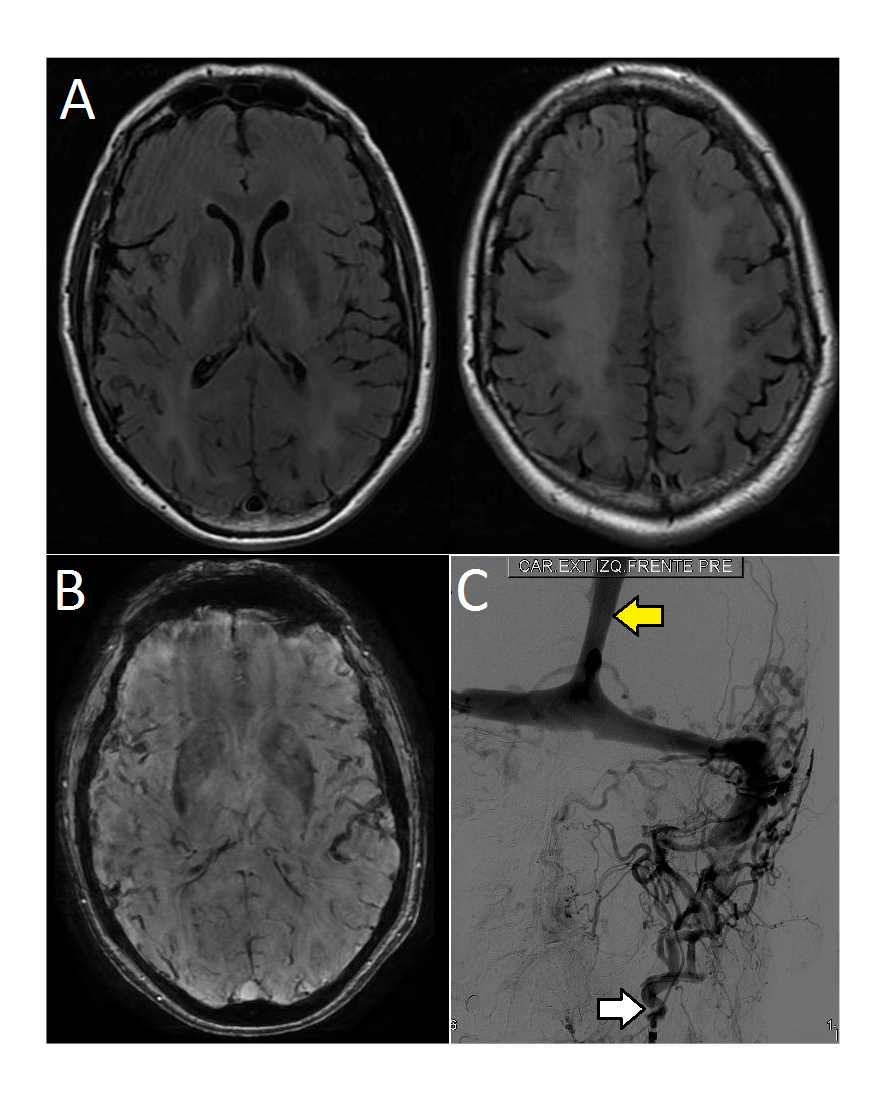

MRI showed extensive bilateral leukoencephalopathy in frontal, parietal and occipital lobes, with hyperintense signal in T2 and hypointense signal in T1 sequences. There was no gadolinium enhancement (Figure 1A, Figure 1B). Additionally, tortuous vessels around the left carotid internal artery near the jugular foramen were observed. It had increased signal in 3D-TOF in the homolateral rectus, transverse and sigmoid sinuses, suggesting a dural arteriovenous fistula with high venous pressure.

Diagnosis of left temporo-occipital DAVF was confirmed with digital subtraction angiography. It revealed occipital artery afference and drainage to the sigmoideus sinus with retrograde flow to the longitudinal superior sinus and deep veins (Figure 1C).

Figure 1.

Source: Authors.